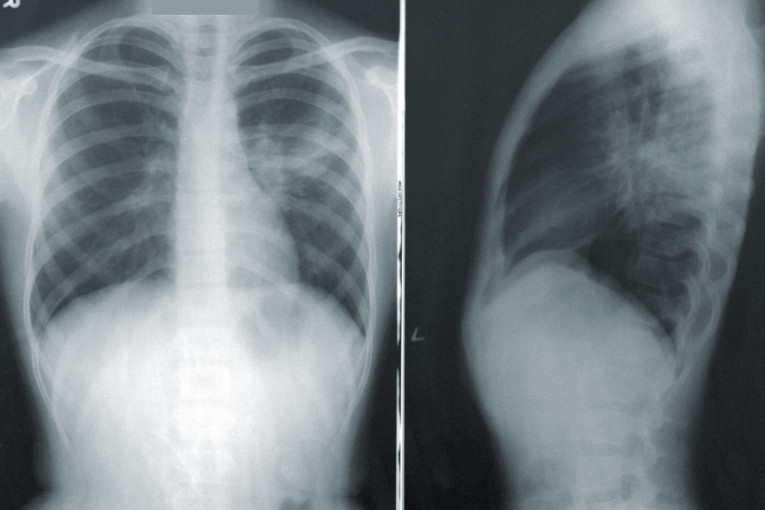

Skrining program podrazumeva detekciju karcinomapluća pomoću niskodoznog skenera (LDCT), uz pomoć kojeg se se mogu prikazati manje tumorske senke, koje nije moguće videti uobičajenim dijagnostičkim postupcima (RTG).Ovom metodom do sada je pregledano više od 1.200 pacijenata, a kod više od 30 otkriven je karcinom pluća koji je bio asimptomatski i u najvećim broju u početnom stadijumu.

- Ukoliko se tumor odstrani u ranom stadijumu, petogodišnje preživljavanje je 66 do 82 odsto. Svesni smo da je rešenje za smanjenje smrtnosti, rano otkrivanje raka. Skrining podrazumeva detekciju pomoću niskodoznog skenera (LDCT), uz pomoć kojeg se se mogu prikazati manje tumorske senke, koje nije moguće videti uobičajenim dijagnostičkim postupcima (RTG). Ovom metodom obuhvatamo visokorizične grupe, u koje spadaju osobe starije od 50 godina, pušači, kao i oni koji imaju porodičnu istoriju obolevanja od raka pluća ili druge hronične plućne bolesti. Na ovaj način, zemlje koje već sprovode LDCT skrining smanjile su mortalitet od raka pluća i do 40 odsto - napominje dr Goran Stojanović upravnik klinike za pulmološku onkologiju, Instituta za plućne bolesti Vojvodine.